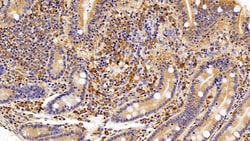

IBA1 Polyclonal Antibody for Western Blot, IHC (P)

Ionized calcium-binding adapter molecule 1 (IBA1), also known by its gene name AIF1, is a protein expressed predominantly by microglia in the brain and spinal cord. This protein belongs to the EF-hand calcium-binding protein family and plays a crucial role in microglial activation and migration in response to brain injury or neuroinflammation. IBA1's function is integral to microglial motility and phagocytic activity, facilitating the cellular response to pathogenic stimuli and promoting tissue homeostasis and repair in the central nervous system. IBA1 serves as a reliable marker for activated microglia in various neurological disorders, including Alzheimer's disease, Parkinson's disease, and multiple sclerosis, where increased expression correlates with disease progression and severity. The protein's structural features enable it to bind calcium ions, inducing conformational changes that activate signaling pathways essential for microglial function. Its expression is highly regulated by inflammatory cytokines, underpinning its role in neuroimmune responses. Due to its specific expression in microglia during pathological conditions, IBA1 is widely used in research as a marker to study microglial status and activity, and it remains a focal point for understanding microglial involvement in neurodegenerative diseases.Specifications

| Immunohistochemistry (Paraffin), Western Blot | |